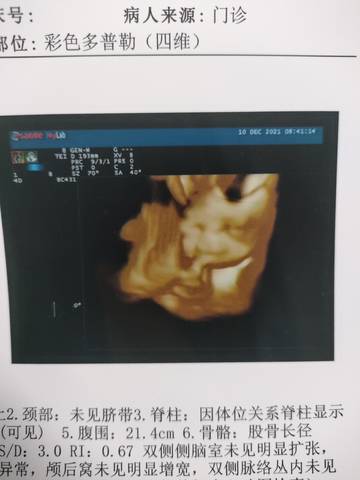

26+1 今天做了四维,有经验的宝妈帮忙看看是男宝还是女宝?

journal_insert_pic_1677352360journal_insert_pic_1677352386